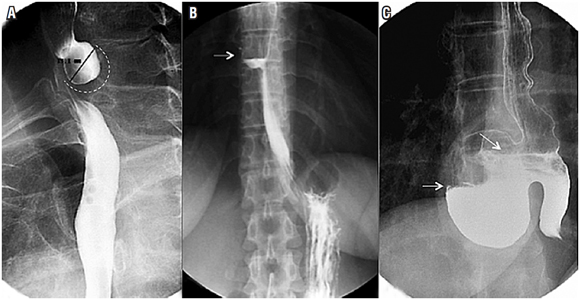

Hernia hiatal

La hernia hiatal es una protrusión del estómago a través del hiato esofágico al tórax que afecta del 10% al 50% de la población, y su diagnóstico y tratamiento tempranos previenen enfermedades de mayor complejidad 11,12. En la evaluación final del esofagograma, se debe identificar la presencia de hernias hiatales, definidas como un tamaño mayor de 2 cm entre la unión esofagogástrica y el hiato diafragmático (si es menor de 2 cm, la herniación es fisiológica) 11,12. El 95% de las hernias primarias son de tipo I (deslizadas) y los tipos II, III y IV se agrupan en las hernias paraesofágicas (más del 90% son de tipo III, y las menos comunes corresponden al tipo II). El reparo laparoscópico es el estándar de tratamiento, y el esofagograma es de utilidad para establecer el tamaño de la hernia, puesto que se requiere una amplia disección esofágica, el cierre adecuado del hiato (posible uso de malla) y un mecanismo antirreflujo 11,12 (Figura 4).

Vólvulo gástrico

El vólvulo gástrico es una rotación anormal (más de 180º) del estómago sobre sí mismo. El vólvulo gástrico agudo es una emergencia quirúrgica, su tratamiento requiere descompresión y devolvulación gástrica y no permite la realización de un estudio radiológico con medio de contraste debido al alto riesgo de aspiración 12. Cuando su presentación es crónica (generalmente, con síntomas de regurgitación, pirosis, dolor precordial y disfagia), el esofagograma, como parte del estudio sintomático, permite la evaluación de la anatomía para determinar la presencia de la hernia, el tamaño y su eje de rotación 11,12.

Los vólvulos gástricos se clasifican en tres tipos (9) (Figura 5):

Mesenterioaxial (rotación sobre el eje del mesenterio).

Organoaxial (rotación sobre su propio eje).

Mixto